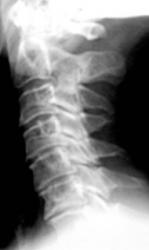

Иллюстрации 1, 2, 3. Определяется «выпрямленность» шейного лордоза, неравномерное сужение межпозвонковых щелей в сегментах С2-С3, С3-С4. Резкое сужение межпозвонковых щелей в сегментах С4-С5, С5-С6, С6-С7, с выраженным субхондральным склерозом тел позвонков, неровностью замыкательных пластинок, образованием остроконечных остеофитов по передней поверхности тел позвонков. В дугоотросчатых суставах определяется сужение суставных щелей с выраженным субхондральным склерозом. На иллюстрации 2 хорошо дифференцируется остеосклеротическая перестройка тел С4, С5, С6, С7, как компенсаторная приспособительная реакция, в результате анатомической и функциональной несостоятельности межпозвонковых дисков.